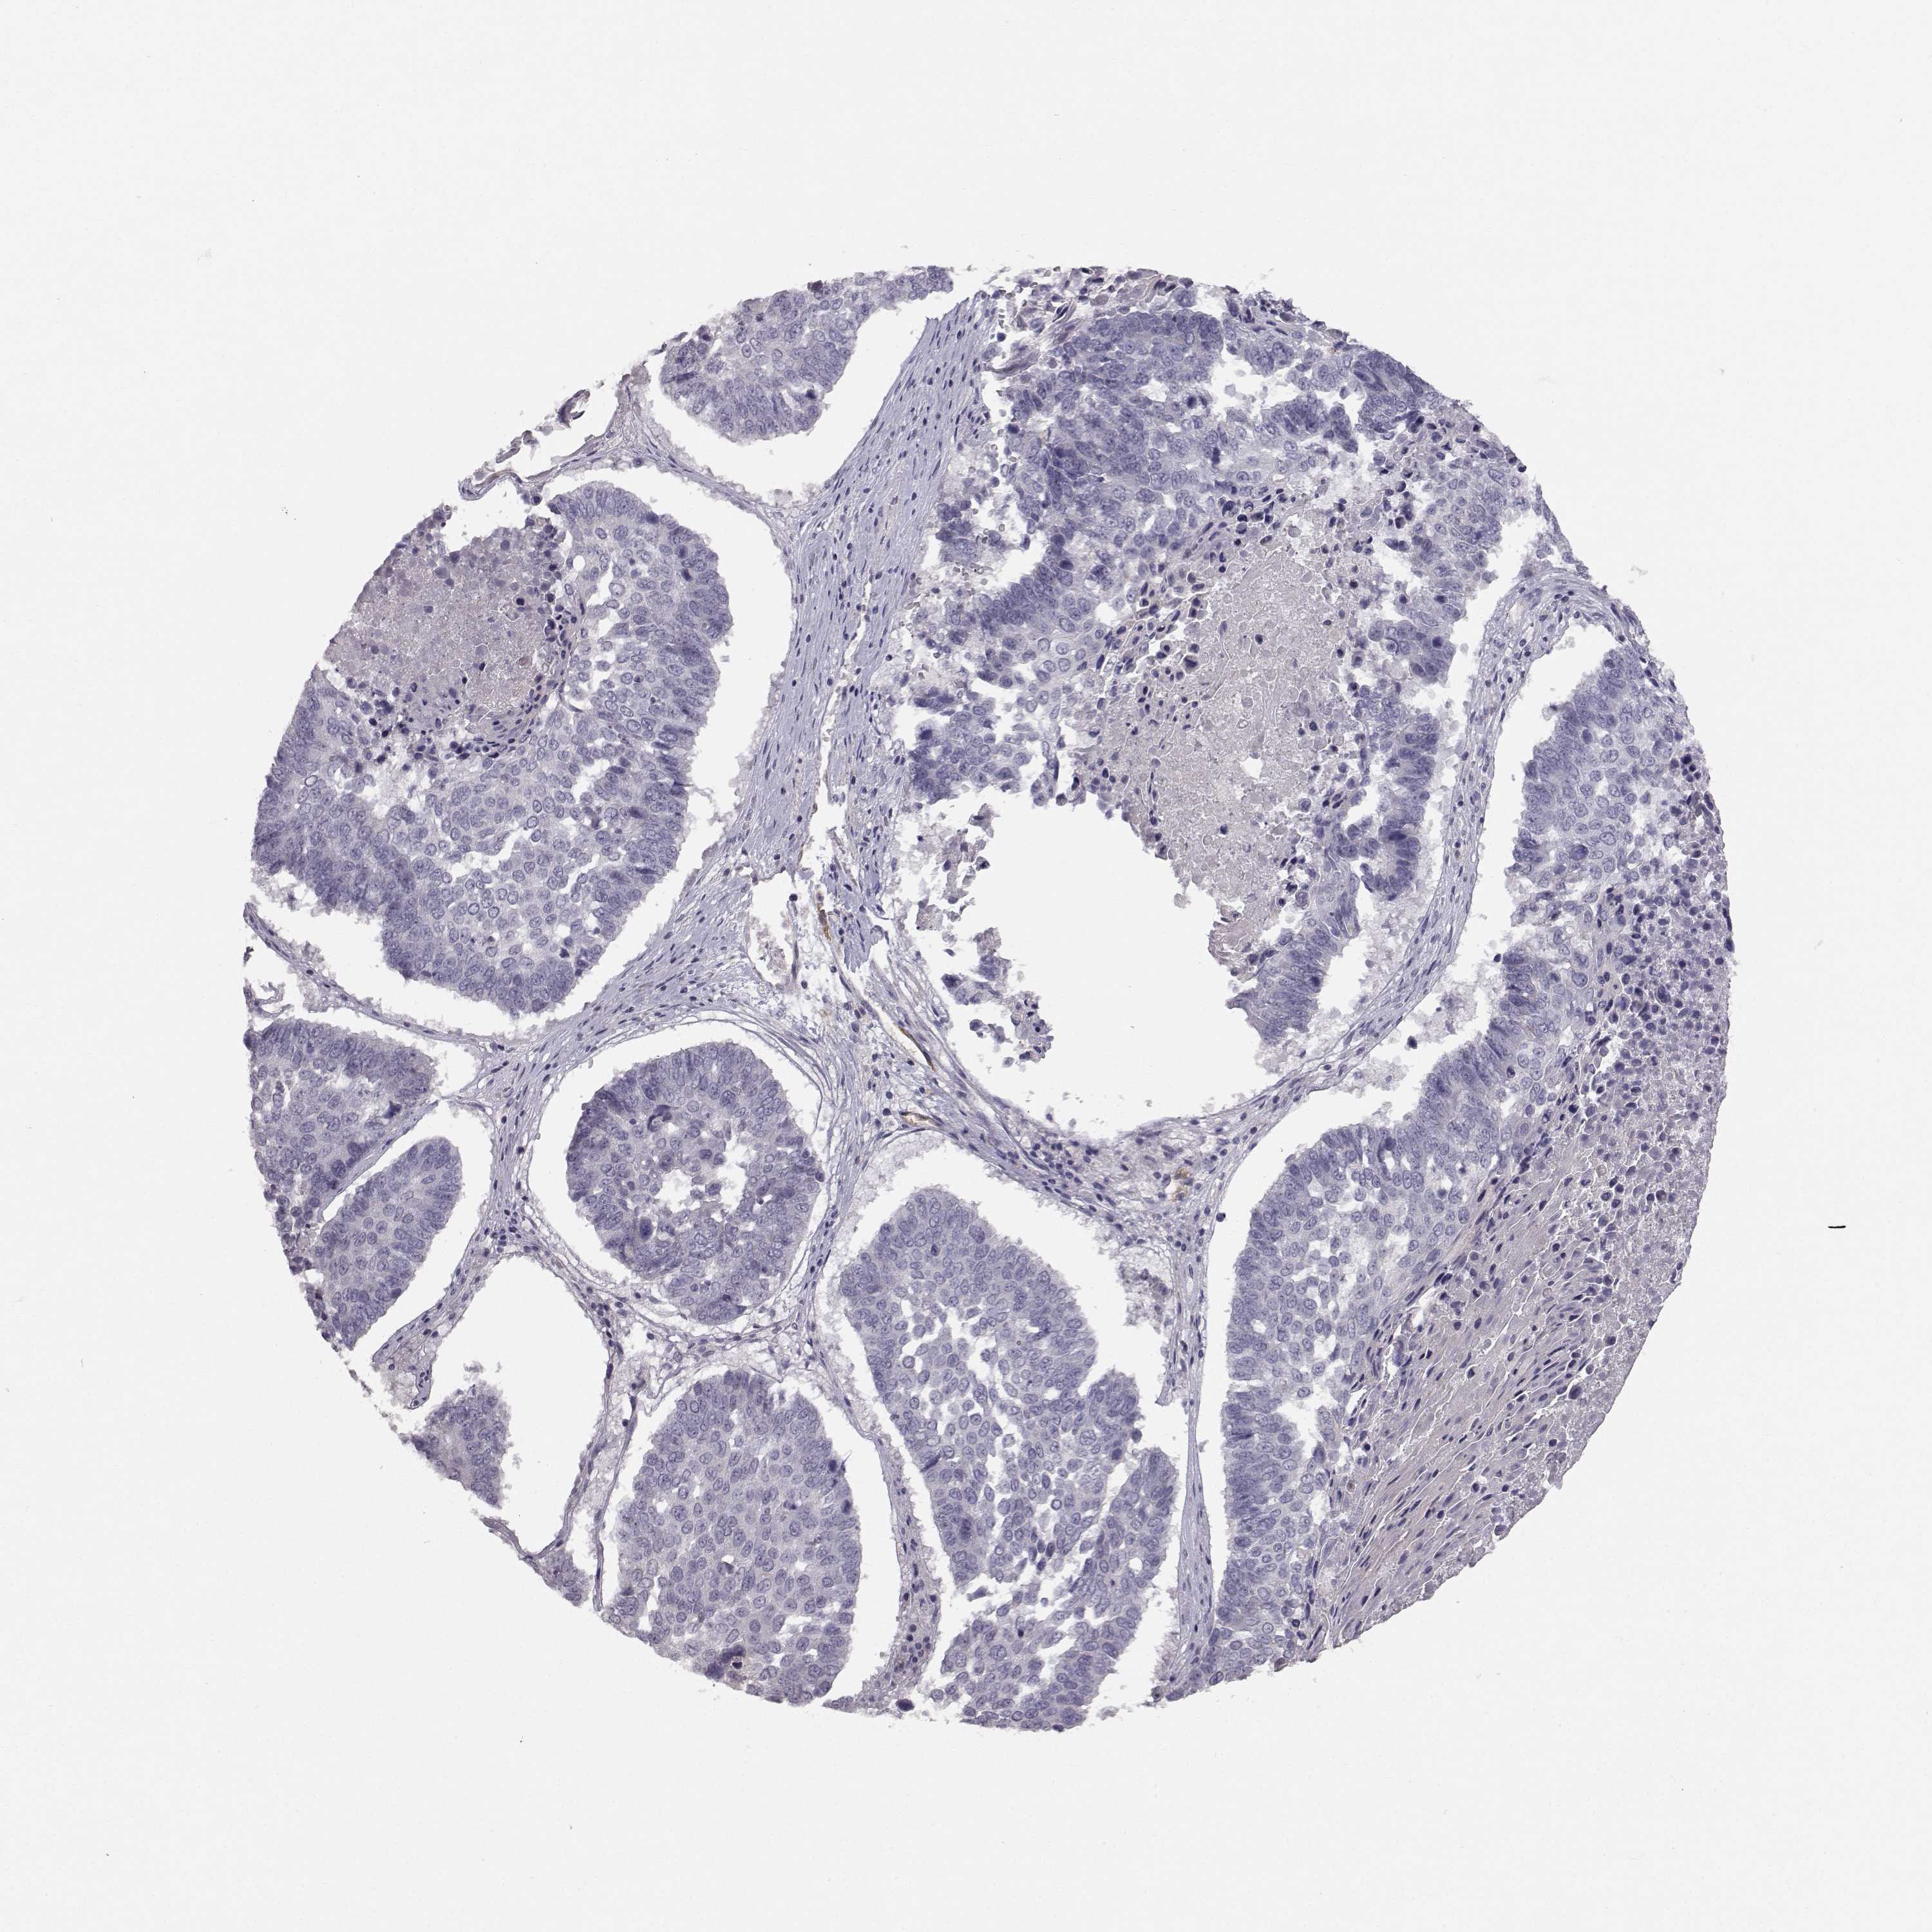

CANCER LUNG CANCER Show tissue menu